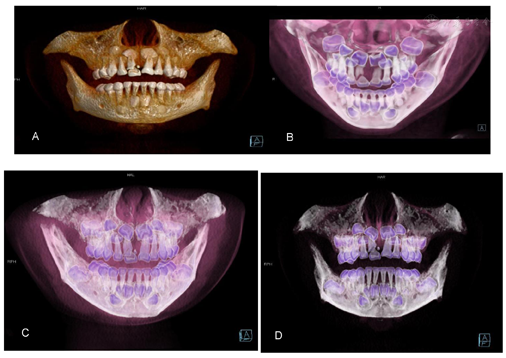

点击查看大图

图4

A~D CT VRT重建位 显示断裂牙齿整体状况